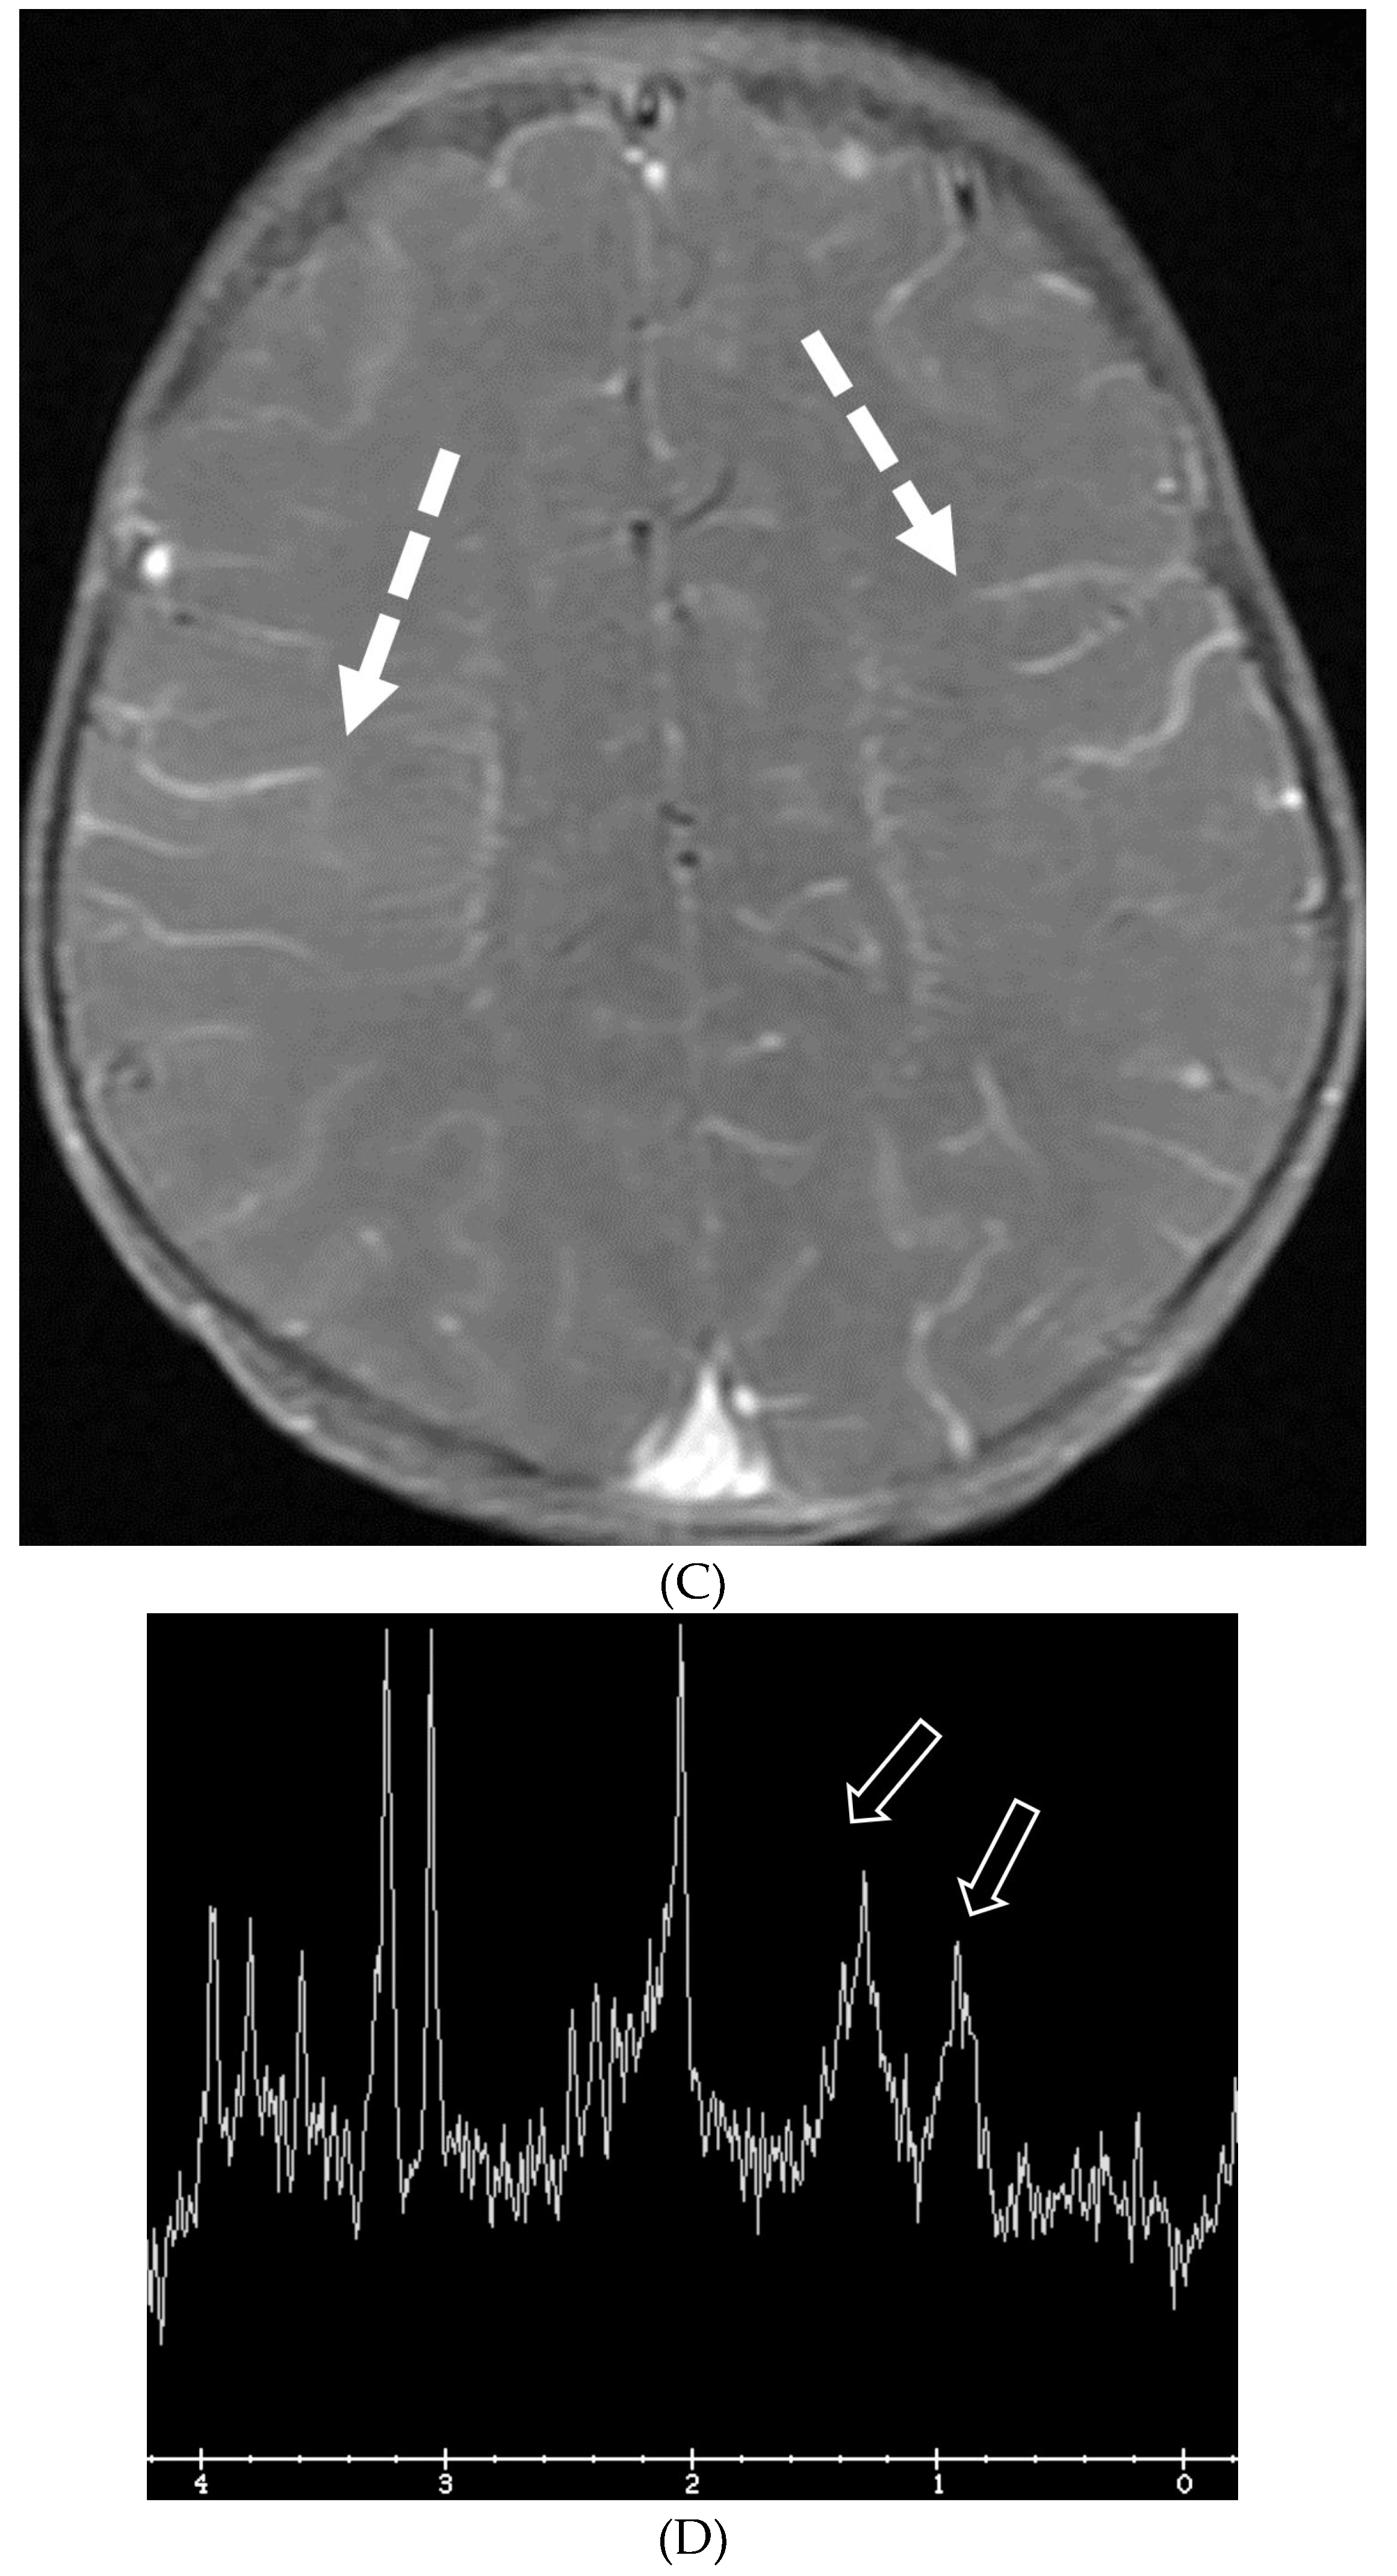

MOYA MOYA

- Horie N, Morikawa M, Nozaki A, Hayashi K, Suyama K, Nagata I. "Brush Sign" on susceptibility-weighted MR imaging indicates the severity of moyamoya disease. AJNR Am J Neuroradiol. 2011 Oct;32(9):1697-702. Epub 2011 Jul 28. PMID: 21799039; PMCID: PMC7965393. [CrossRef]

- Ohta T, Tanaka H, Kuroiwa T. Diffuse leptomeningeal enhancement, "ivy sign," in magnetic resonance images of moyamoya disease in childhood: case report. Neurosurgery. 1995 Nov;37(5):1009-12. PMID: 8559324. [CrossRef]

- Maeda M, Tsuchida C. "Ivy sign" on fluid-attenuated inversion-recovery images in childhood moyamoya disease. AJNR Am J Neuroradiol. 1999 Nov-Dec;20(10):1836-8. PMID: 10588105; PMCID: PMC7657767.

- Liu ZW, Han C, Wang H, Zhang Q, Li SJ, Bao XY, Zhang ZS, Duan L. Clinical characteristics and leptomeningeal collateral status in pediatric and adult patients with ischemic moyamoya disease. CNS Neurosci Ther. 2020 Jan;26(1):14-20. Epub 2019 Apr 13. PMID: 31875482; PMCID: PMC6930821. [CrossRef]

- Komiyama M, Nakajima H, Nishikawa M, Yasui T, Kitano S, Sakamoto H. Leptomeningeal contrast enhancement in moyamoya: its potential role in postoperative assessment of circulation through the bypass. Neuroradiology. 2001 Jan;43(1):17-23. PMID: 11214642. [CrossRef]